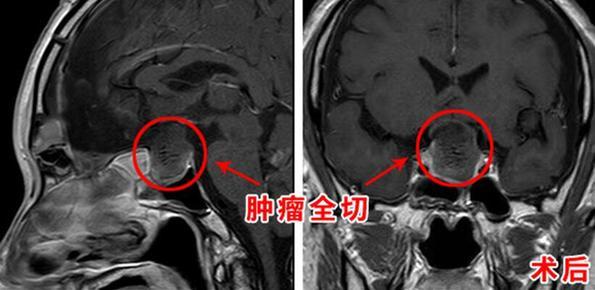

垂体危象是怎么形成的(当垂体瘤遇上卒中命悬一线通宵抢救终于转危为安)

我们都知道,卒中一般是指由脑血栓、脑出血等引起,它发病突然,短时间内达高峰,多是脑部血管突然破裂或阻塞引起的急性脑组织损伤,不少情况下,卒中可导致残疾,甚至死亡。然而,有一种卒中,却是由于特殊的肿瘤也会引起。日前,一...